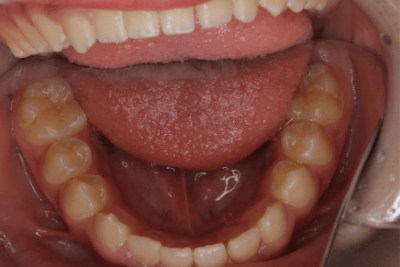

3.叢生(そうせい)、でこぼこ

叢生とは、歯並びがデコボコの状態のことを指します。

歯並び・かみ合わせが悪い状態を不正咬合といいます。

その不正咬合の原因はひとつではありません。

詳しくは「叢生(そうせい)」をご確認ください